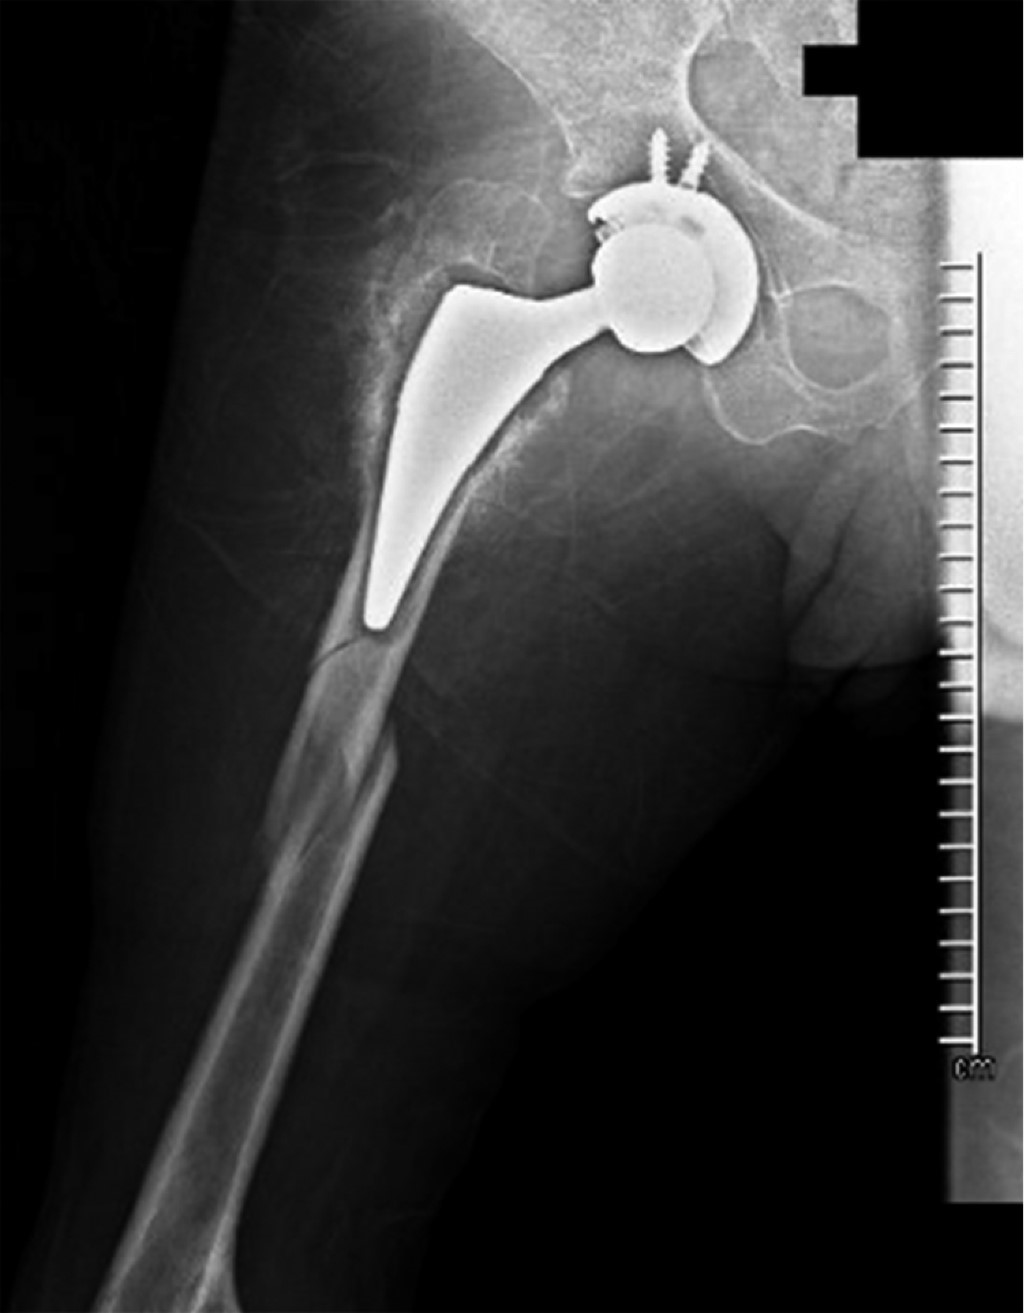

Periprosthetic fracture in a patient with polio sequelae: a case report

Introduction: poliomyelitis paralyzed thousands of children during the 20th century. However, due to mass vaccination its eradication was achieved. Today it is estimated that there are 12 - 20 million people with polio sequelae (PWPS) who make up a risk group for pathological fractures, as a consequence of muscle degeneration and osteopathy. There is no consensus on its treatment. The aim of this report is to demonstrate the problem of fracture management in PWPS. Additionally, an option for the treatment of a periprosthetic fracture in this population is proposed. Presentation of case: 46-year-old male PWPS with pain in the right lower extremity after falling from a chair, with a history of right hip arthroplasty six months ago due to a transcervical fracture. Radiographically, a Vancouver C periprosthetic fracture is seen. Open reduction of the fracture is performed and an anatomical cable-type locking compression plate and cerclage cables are placed. An adequate radiographic evolution is observed. Conclusions: polio is an eradicated disease; however, it should not be ignored since PWPS are a risk group for fractures in pathological terrain. Treatment of these types of fractures and their complications is a challenge. There is a pressing need for comprehensive clinical and surgical guidelines to guide their approach.

Figure 1